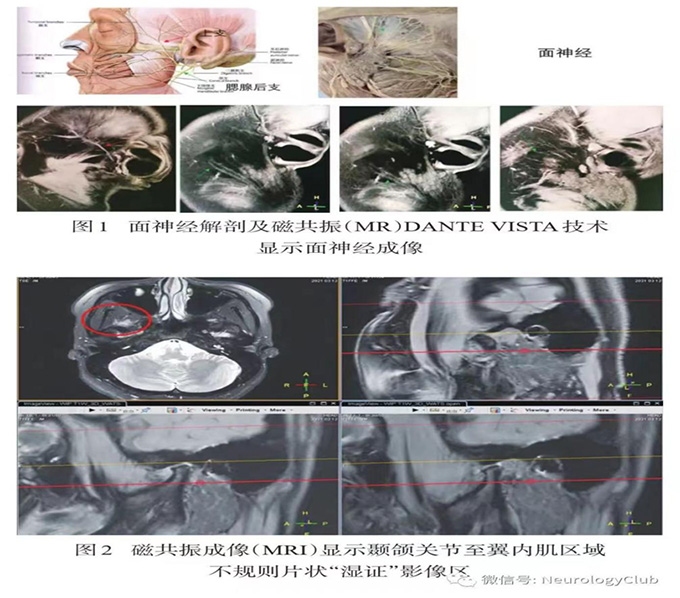

根据面神经的特点,面神经的发病部位一般分为六段,如图:

核上性病变往往表现出中枢性面瘫,面神经核损害往往会伴有其他神经核的损害,因此可能会有走路不稳及眼球运动障碍等情况。周围性面神经损害主要有:①膝状神经节前损害:鼓索神经损害,舌前2/3味觉障碍;镫骨肌神经分支损害,出现听觉过敏;②膝状神经节病变又叫“亨特氏面瘫”,不仅表现有面神经麻痹、听觉过敏和舌前2/3味觉障碍,还有耳廓和外耳道感觉迟钝、外耳道和鼓膜上出现疱疹,为带状疱疹病毒感染相关;③茎乳孔附近病变(茎突孔位于耳后,以上为颅骨以内):会出现上述周围性面瘫的体征以及耳后区压痛感。整个面神经长度约为140mm,按照神经修复的速度,每天大约可以修复1mm,因此损害的部位越往颅内、脑干方向时间就越长,这也就是为何有的人1个周就好了,有的人半年了都没好。当然除了发生损害的部位,恢复的时间还和神经损害的程度、治疗的正确与否有关,如果神经纤维已经完全断裂,那么恢复的可能性就微乎其微了。据研究,面瘫大部分会在1—2个月内康复,部分会在3个半月前康复,3个半月未康复往往会进入面瘫的联带运动,即前图B所示;只有极少部分人能在一周内恢复。

面瘫应规范的诊断和治疗,完善“颅脑CT及核磁共振”是为面瘫的安全诊治提供保障,曾有面瘫两月不愈,完善头颅CT才发现是颅内肿瘤占位压迫,最后手术治疗,费时费力费钱。在排除颅内占位性病变等继发面瘫的前提下,也可在发病后一周,神经水肿基本消退后进一步完善肌电图等检查,了解神经损害程度,以便医生对面瘫治疗的预后作出判断。